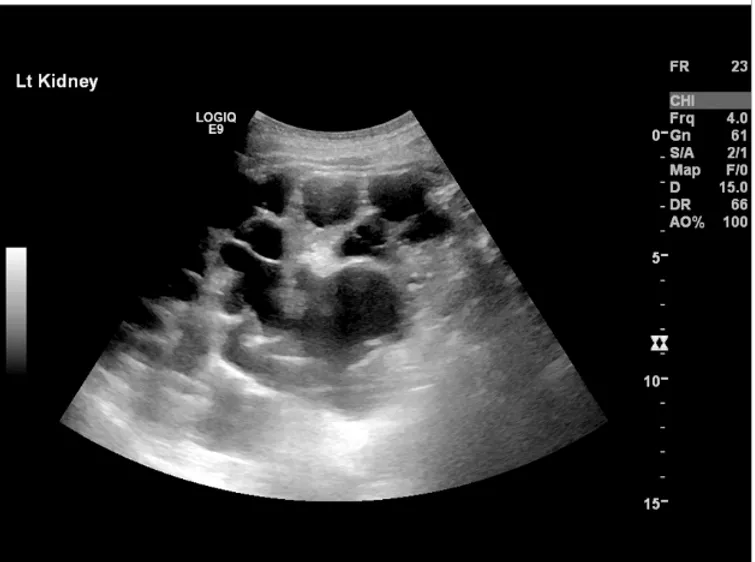

DRPAD além do Tolvaptana: Novas Perspectivas Terapêuticas nas Diretrizes KDIGO 2025

Além do tolvaptana, as diretrizes KDIGO destacam a importância de medidas não farmacológicas e abordagens complementares no manejo da DRPAD, como controle rigoroso da pressão arterial, redução de ingesta de sal e aumento de ingestão hídrica. Estudos em andamento também avaliam terapias-alvo envolvendo vias do mTOR, cAMP e inflamação. O manejo multidisciplinar permanece essencial para retardar a progressão da doença e melhorar a qualidade de vida.

Uso do Tolvaptan na DRPAD: O Que falam nas Novas Diretrizes KDIGO 2025?

As novas diretrizes KDIGO para a Doença Renal Policística Autossômica Dominante (DRPAD) atualizam os critérios de elegibilidade para o uso de tolvaptana, com ênfase na estratificação do risco de progressão rápida. O documento reforça a individualização da terapia com base em subclassificação por imagem (Mayo Clinic) e função renal. A incorporação prática dessas recomendações pode otimizar o manejo e retardar a progressão da DRC nesses pacientes.